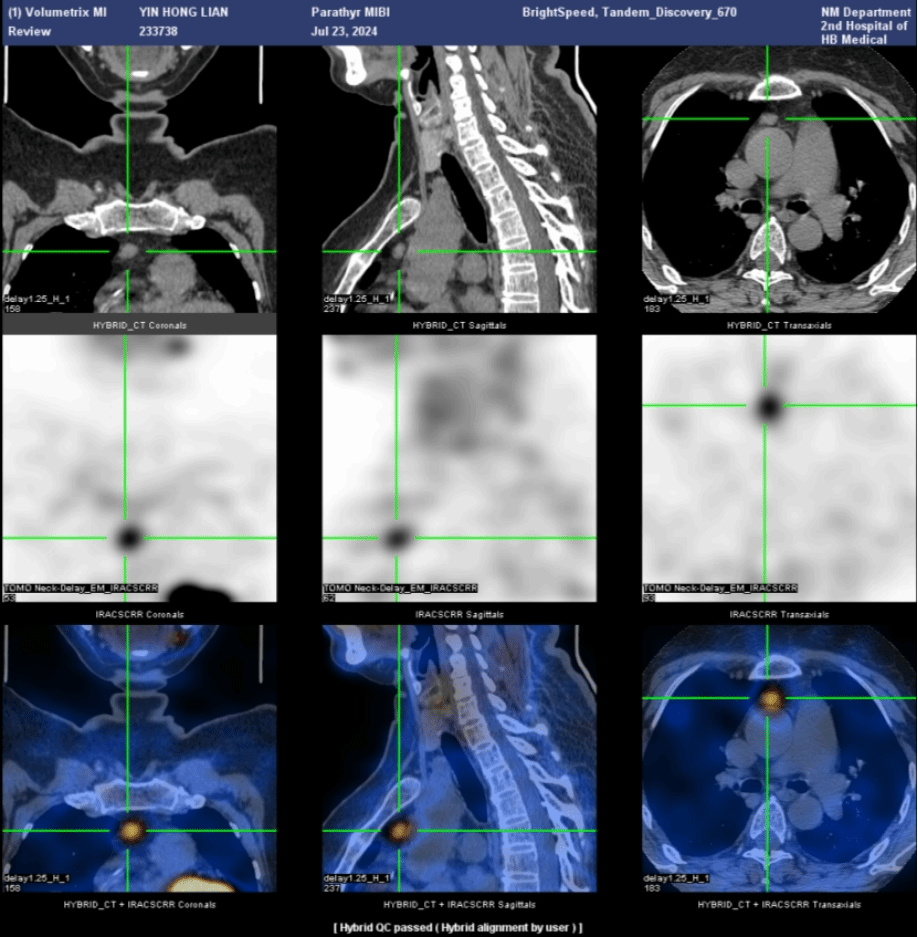

为了明确病变的位置,段阿姨又进行了核医学科的甲状旁腺显像(图5):

左侧甲状旁腺区显像剂浓聚较对侧稍增强,消退缓慢,提示可能为左侧甲状旁腺病变。

进一步的SPECT/CT断层融合显像(图6)显示,左上甲状旁腺形态增大,呈长条形,大小约1.3cm×0.6cm×4.5cm,并伴显像剂异常浓聚,考虑为功能亢进的甲状旁腺病变,首先考虑腺瘤。

后来段阿姨进行了手术治疗,病理为甲状旁腺腺瘤,术后段阿姨的血清钙恢复正常,PTH降低。